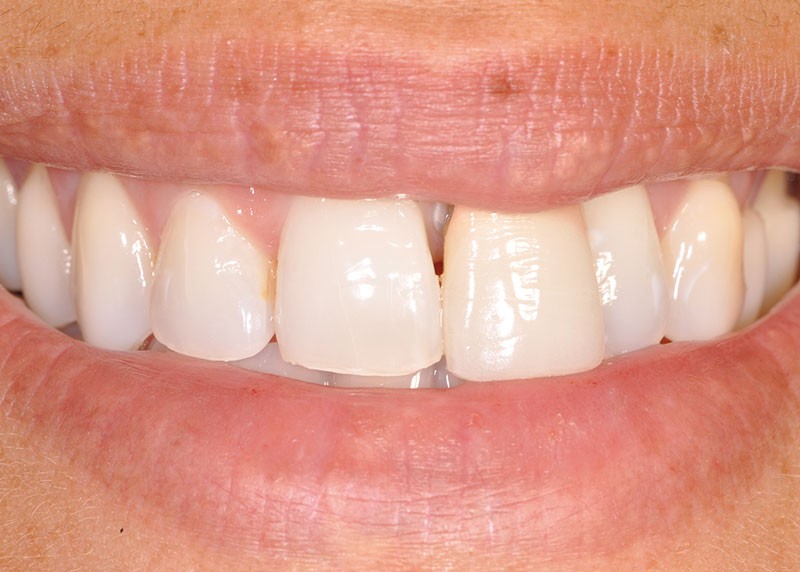

Une patiente âgée de 32 ans, en bonne santé générale et non fumeuse, est adressée pour réhabilitation esthétique et fonctionnelle du secteur antérieur, conséquence d’un trauma facial remontant à seize ans, au cours duquel la dent 21 a été expulsée et réimplantée. Dans un souci esthétique, deux couronnes céramo-métalliques ont été fabriquées successivement au cours du déplacement progressif de la dent.

L’examen clinique montre que l’incisive centrale maxillaire gauche (21) est en exfoliation vestibulaire, elle présente une mobilité 2 de sa portion coronaire et interfère dans sa fonction (fig. 1, 2).